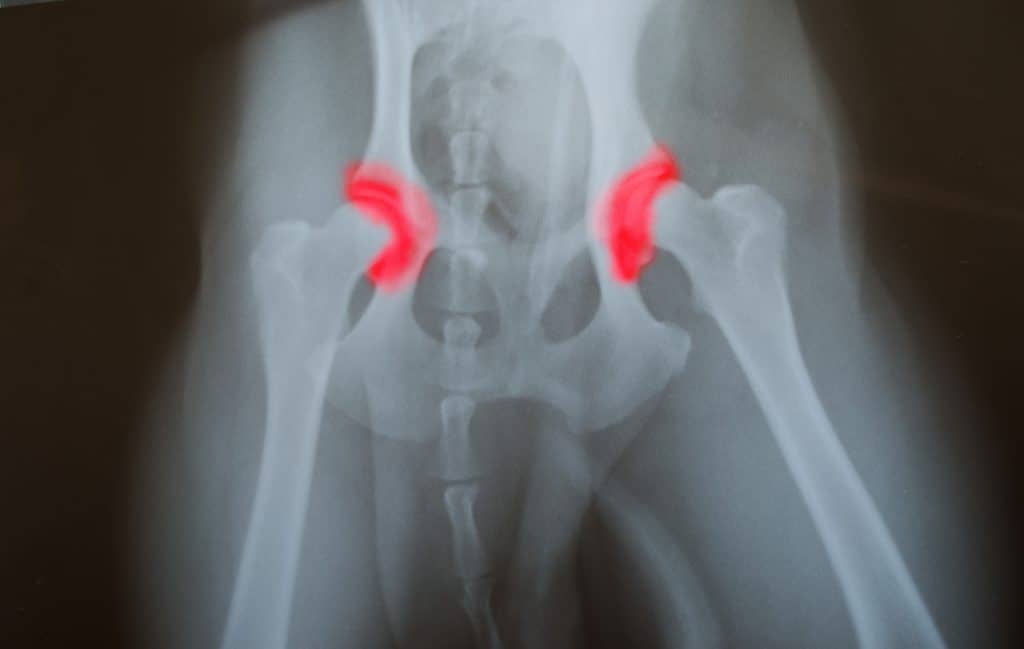

It may be that you suspect that your Labrador is showing symptoms of dysplasia in the elbows or hips, but you won’t know for sure. Take your pet to a vet to get them properly checked over. Using radiography, arthroscopy, X-rays, or computed tomography, the vet will be able to look at the hip and elbow joints more closely. They’ll then be able to diagnose the condition with accuracy. They’ll also categorize exactly which type of dysplasia your dog is experiencing.